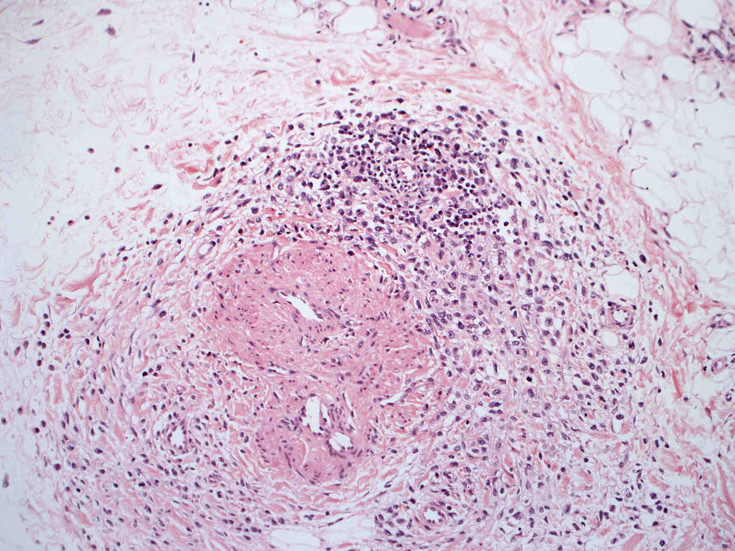

皮膚生検組織。細胞浸潤が表皮, 表皮真皮境界部, 真皮, 皮下組織にびまん性に認められる。血管中心性に結節様の分布があるように見える。

皮膚に異型細胞の浸潤がみられる。異型細胞は表皮内に浸潤するほか、表皮真皮境界部, 真皮, 皮下脂肪組織にもびまん, 結節様の浸潤所見を示す。血管周囲に浸潤、集蔟する所見も多く見られる。 増殖浸潤細胞の核には類円形や腎臓形, またはへこみ, 切れ込み, 溝などを有する多型な核が認められる。クロマチンは粗でvesicularな核が多い。核小体の明らかな核もある。好エオジン性の核内封入体様構造も少数に見られた。mitosisは容易に認められる。hyperchromaticな多型核, bizzarreな細胞が高頻度に認められ異型度は高いと考えられる。細胞質は境界不明瞭, 淡明または泡沫様の 好エオジン性胞体である。